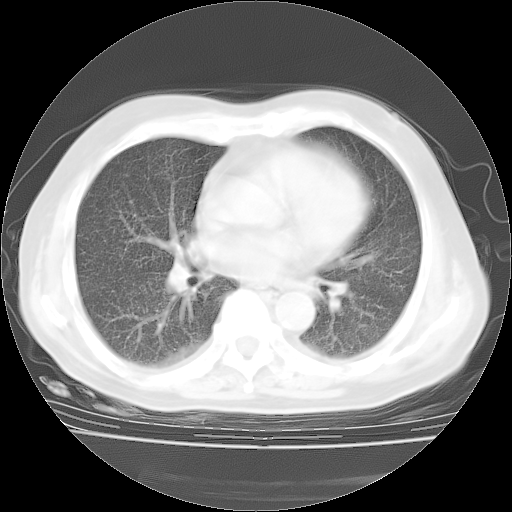

4月28日肺部CT——再次出现类似去年5月9日——透光度降低,“间质性”改变。

4月28日肺部CT——再次出现类似去年5月9日——磨玻璃样、间有“粟粒样”改变。